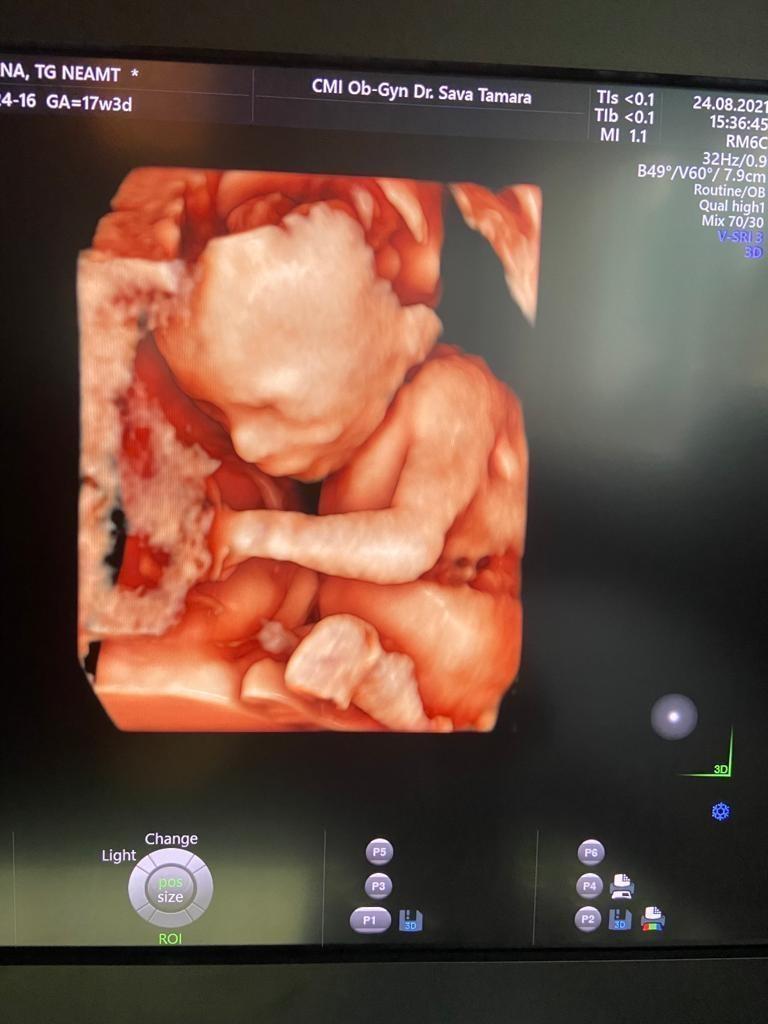

Cabinet individual Obstetrica-Ginecologie - Dr. Sava Tamara

Medic-primar obstetrica-ginecologie, competenta in ecografie obstetricala si ginecologica, colposcopie.

Cabinetul de Obstetrica-Ginecologie Dr. Sava Tamara va ofera o gama larga de servicii de obstetrica-ginecologie, tratand pacientele cu profesionlism intr-un cadru discret, relaxant si intim: consultatie ginecologica, consultatie mamara, ecografie genitala (sonda abdomen, sonda endovaginala), ecografie sarcina, extragere sterilet, montare sterilet, examen citobacteriologic, examen citodiagnostic (Papanicolau), videocolposcopie, teste sarcina etc. Pacientele noastre beneficiaza de consultatie, recomandari si tratamente si sunt atent consiliate, primesc informatii, si raspunsuri la eventualele intrebari.